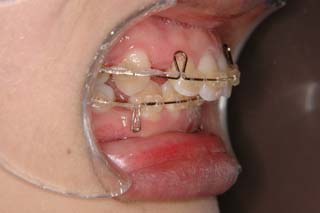

上顎前歯、下顎前歯の前突が見られます。大きな叢生は見られませんが、上下の口唇前突感も伴います。このような不正咬合を上下顎前突と言います。審美的な事もさることながら、歯軸の傾斜の問題から歯にかかるベクトルが良くない事、口唇の筋肉の緊張を強いるような不調和を示す事などから、不正咬合の一つとして考えられています。上顎前突傾向も伴っていますので、積極的に上顎前歯の後退を行う目的で、上顎に固定源となる 目的外使用の オーソアンカー SMAPシステム を装着しました。現在では、歯科矯正用アンカースクリュー(デュアルトップオートスクリュー、ISAアドバンスなど)といった、医療機器認証番号がある製品を用いることが多くなりました。

通常の矯正治療であれば、上顎の固定源として用いるのはヘッドギアという装置です。しかしながら、現状の日本では夜間使用以上の連続使用は難しいでしょう。ちなみにアメリカの学生は、授業中でもヘッドギアを装着してくれるみたいです。さぼり気味な人だと、ヘッドギアの効果が少なく、矯正治療が終わった後なのに、出っ歯の人もいるかも知れません。

歯を抜いた隙間を閉じる時、しっかり留めておかないと前歯が下がるだけでなく奥歯も前に寄ってきます。沢山、前歯を下げたい時には、奥歯と前歯を引っ張るのをやめて、前歯と別の固定源(歯科矯正用アンカースクリューなど)を引っ張ります。